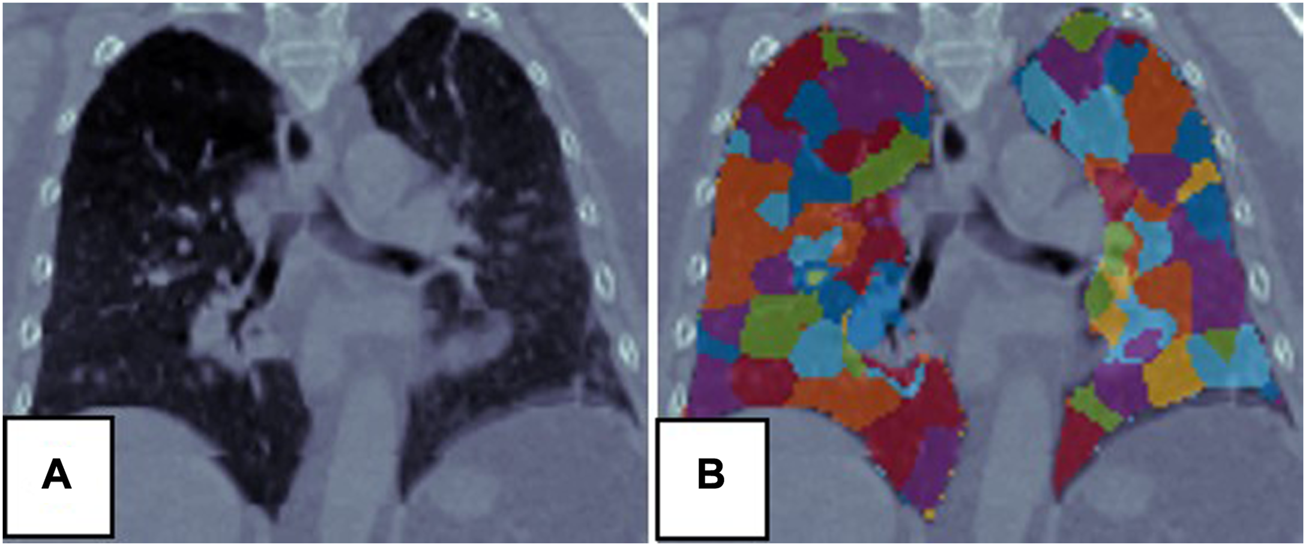

The SLIC method was used to divide the lung volumes of the 21 patients into 380–715 super-voxels at a of 1,500. Figure 3 shows an example of super-voxel segmentation of the lung volume. Different colors indicate different super-voxel regions. The mean correlation between and SPECT was 0.91 (range: 0.84–0.96). Figures 4B, C show a comparison between SPECT and images. The two images have a similar function distribution. The strong correlation between and SPECT suggests that a reasonable CTVI image of the whole lung volume can be generated by analyzing hundreds of super-voxels.

FIGURE 3

Super-voxel segmentation in the lungs of a patient. (A) Is the CT, (B) is the result of the super-voxel segmentation in the lung region.